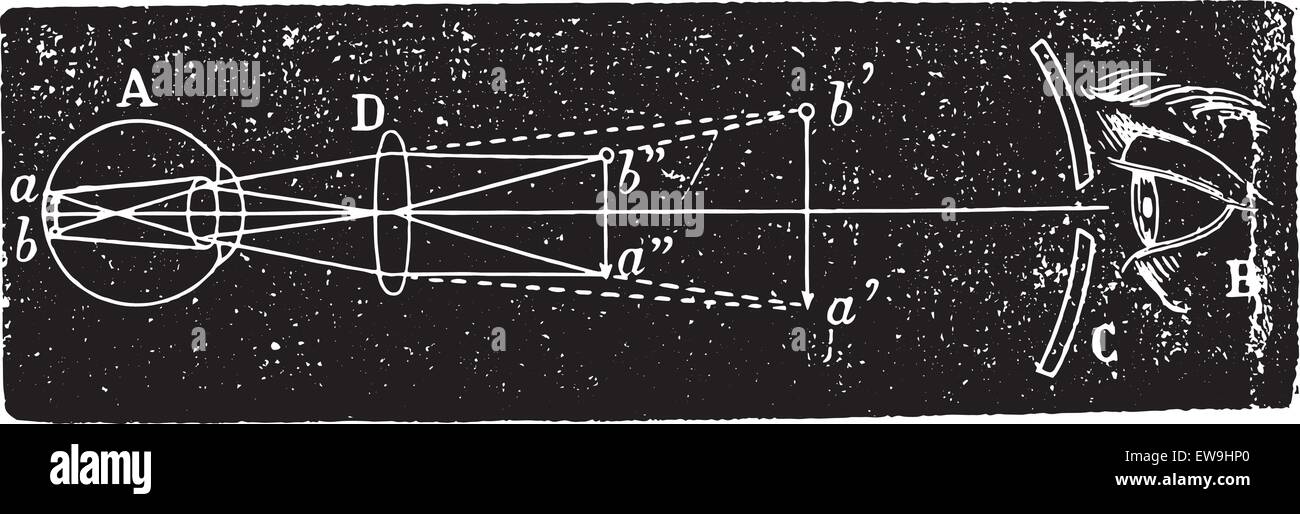

Ophthalmoscope, vintage engraved illustration. Usual Medicine Dictionary - Paul Labarthe - 1885. Stock Vectorhttps://www.alamy.com/image-license-details/?v=1https://www.alamy.com/stock-photo-ophthalmoscope-vintage-engraved-illustration-usual-medicine-dictionary-84406967.html

Ophthalmoscope, vintage engraved illustration. Usual Medicine Dictionary - Paul Labarthe - 1885. Stock Vectorhttps://www.alamy.com/image-license-details/?v=1https://www.alamy.com/stock-photo-ophthalmoscope-vintage-engraved-illustration-usual-medicine-dictionary-84406967.htmlRFEW91XF–Ophthalmoscope, vintage engraved illustration. Usual Medicine Dictionary - Paul Labarthe - 1885.

Ophthalmoscopic examination was the inverted image, vintage engraved illustration. Usual Medicine Dictionary - Paul Labarthe - 1 Stock Vectorhttps://www.alamy.com/image-license-details/?v=1https://www.alamy.com/stock-photo-ophthalmoscopic-examination-was-the-inverted-image-vintage-engraved-84406966.html

Ophthalmoscopic examination was the inverted image, vintage engraved illustration. Usual Medicine Dictionary - Paul Labarthe - 1 Stock Vectorhttps://www.alamy.com/image-license-details/?v=1https://www.alamy.com/stock-photo-ophthalmoscopic-examination-was-the-inverted-image-vintage-engraved-84406966.htmlRFEW91XE–Ophthalmoscopic examination was the inverted image, vintage engraved illustration. Usual Medicine Dictionary - Paul Labarthe - 1

Ophthalmoscopic examination was the inverted image, vintage engraved illustration. Usual Medicine Dictionary - Paul Labarthe - 1 Stock Vectorhttps://www.alamy.com/image-license-details/?v=1https://www.alamy.com/stock-photo-ophthalmoscopic-examination-was-the-inverted-image-vintage-engraved-84419384.html

Ophthalmoscopic examination was the inverted image, vintage engraved illustration. Usual Medicine Dictionary - Paul Labarthe - 1 Stock Vectorhttps://www.alamy.com/image-license-details/?v=1https://www.alamy.com/stock-photo-ophthalmoscopic-examination-was-the-inverted-image-vintage-engraved-84419384.htmlRFEW9HP0–Ophthalmoscopic examination was the inverted image, vintage engraved illustration. Usual Medicine Dictionary - Paul Labarthe - 1